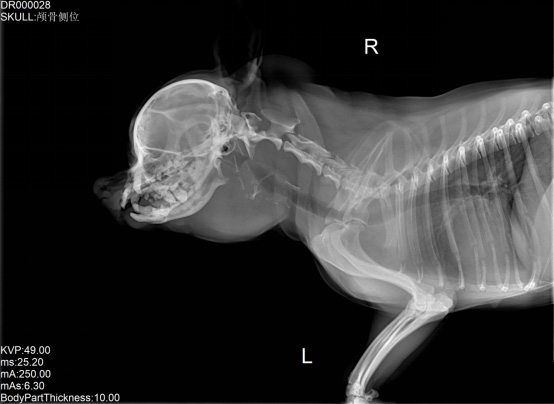

寵物DR是專業用于寵物X光拍攝的數字化X射線檢查,輔助寵物醫生進行及時精確的診療。寵物DR主要包括五大主要部件,數字X光探測器,高壓發生器,球管,機架,寵物專用的DR工作站軟件。寵物DR由于采用數字技術,自動成像處理,模擬X線圖像向數字化X線圖像的轉變。寵物DR與傳統模擬X光機相比有什么優勢呢?采集時間10毫秒以下,成像時間僅為3秒,較高的空間分辨力和低噪聲率,提高了病灶的檢出率,避免漏診誤診等問題。減少X線對人體照射的不良影響寵物DR照片是您最佳的選擇。提高寵物醫生工作效率,總而言之,選擇寵物DR是寵物醫院的最佳選擇。寵物醫學影像學實現全數字化和無膠片化升級發展提高技術水平。